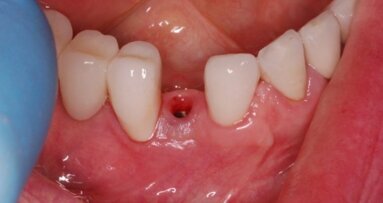

Wstępny etap leczenia obejmował usunięcie zęba 13 z użyciem techniki piezoelektrycznej z następową augmentacją powstałej jamy kostnej oraz ekstrakcję zniszczonego procesem próchnicowym zęba 53 (Ryc. 9). Dzięki przedprotetycznemu leczeniu ortodontycznemu uzyskano wymaganą przestrzeni dla implantokorony.

Po 6-miesięcznym okresie wgajania implantu wykonano tymczasową koronę kompozytową osadzoną na tytanowym łączniku tymczasowym w celu ukształtowania profilu wyłaniania korony. Po 3-miesięcznym okresie użytkowania korony tymczasowej wykonano ostateczne uzupełnienie protetyczne – koronę całoceramiczna LAVA cementowaną na indywidualnym łączniku frezowanym z dwutlenku cyrkonu (Ryc. 10 i 11).